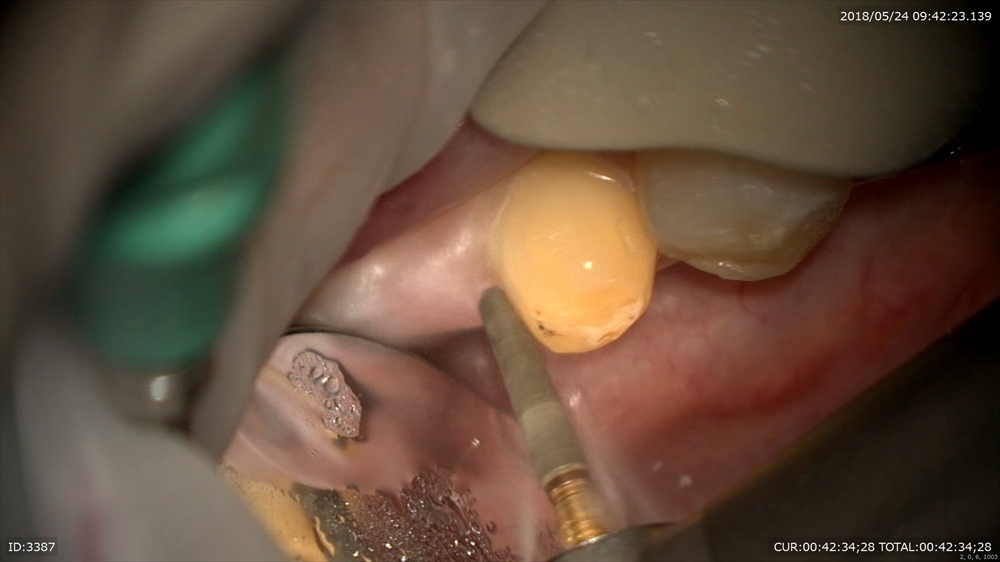

次のケースはブリッジの形成から仮歯を作成。

ブリッジの為無痛で整え

仮歯を作成